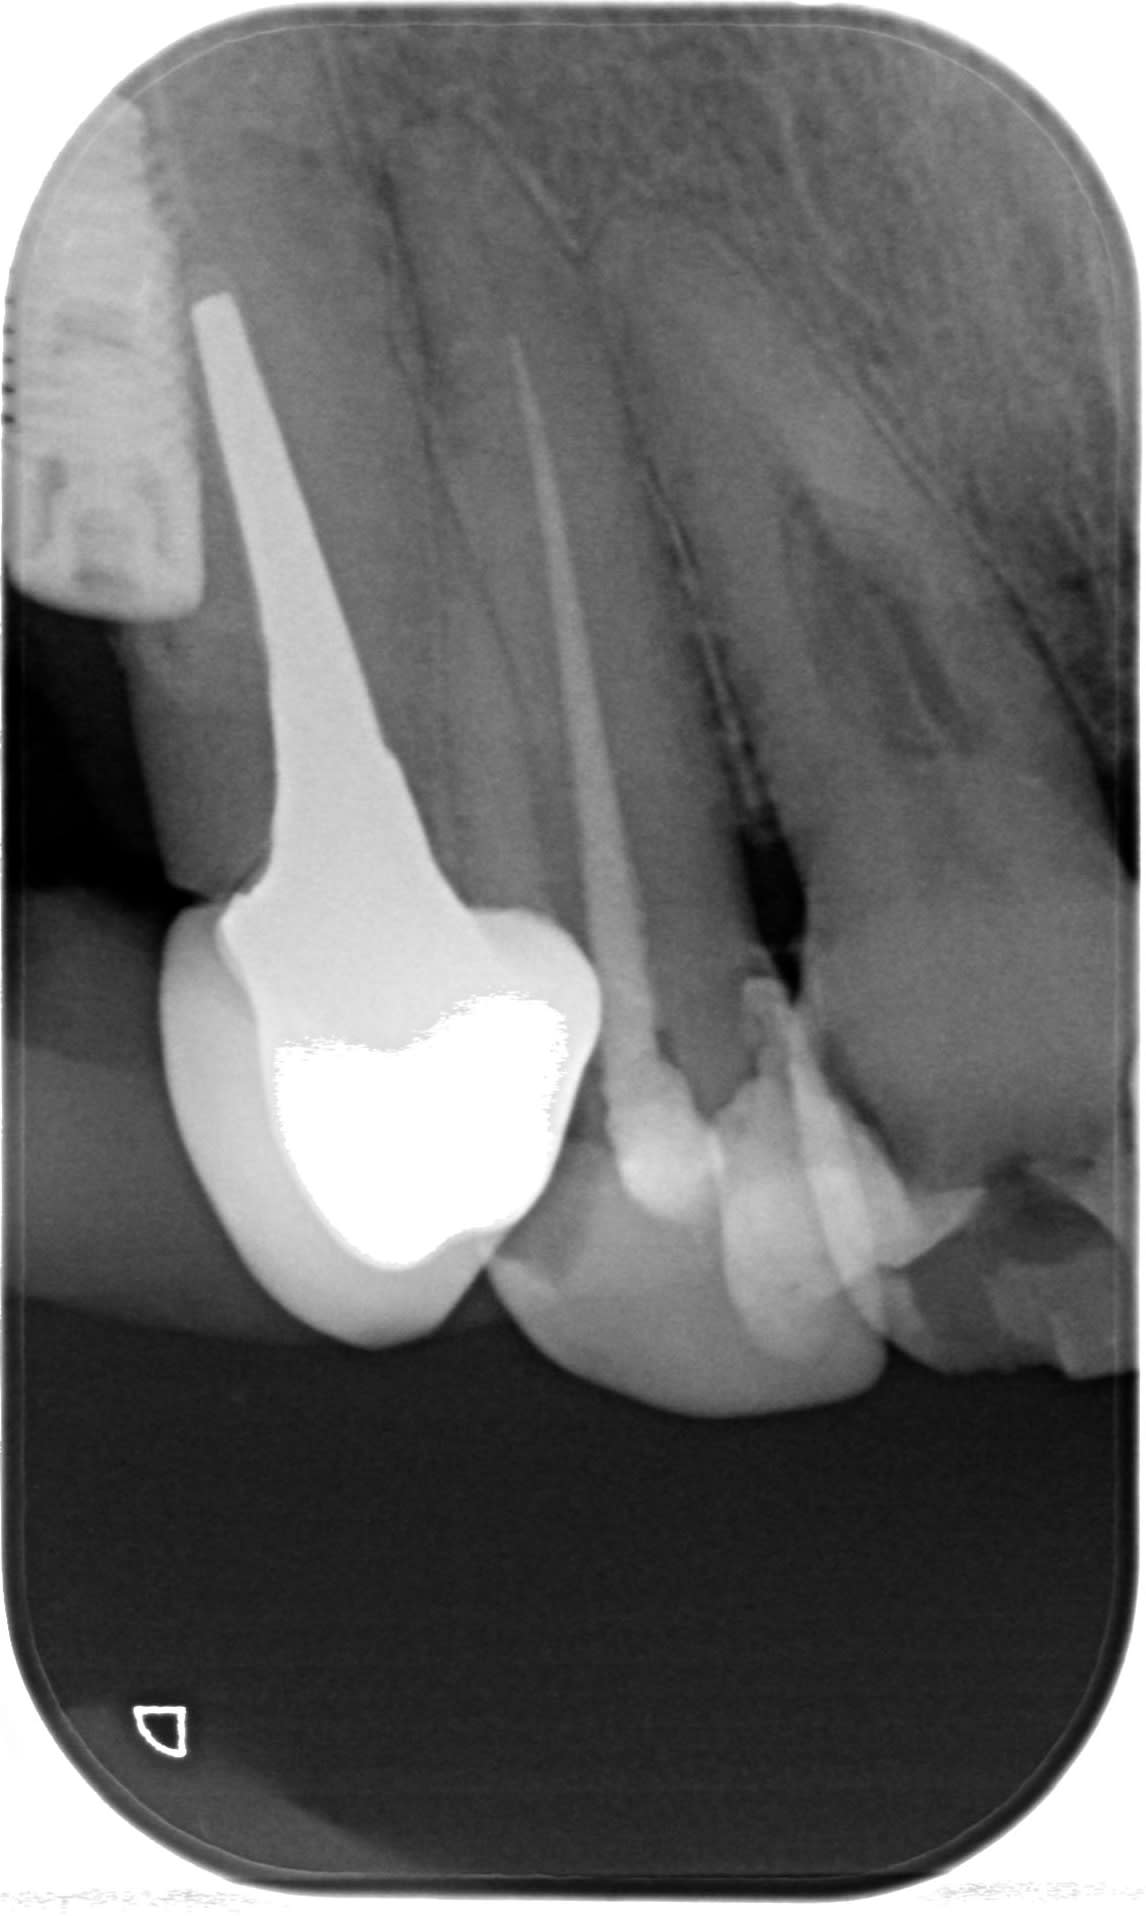

Sur 14, un TSV?

Photo pluton1b h9n4ea - Eugenol

ouaip

16 aussi